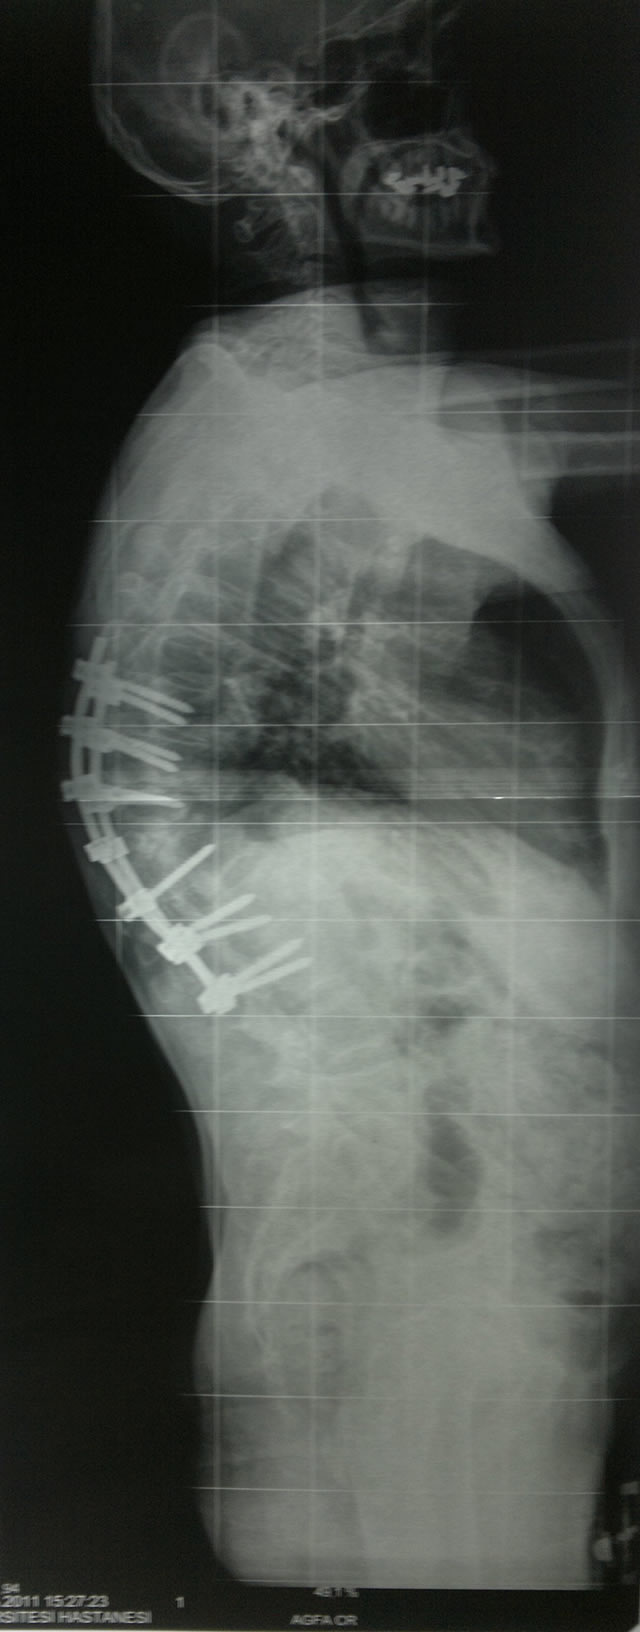

Omurga veremi sonucu kifoz oluşan hastanın ameliyat öncesi ve sonrası filmleri: